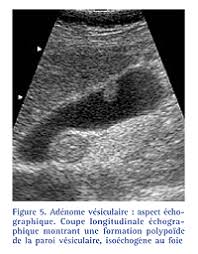

Résumé l'adénomyomatose (adm) vésiculaire est une anomalie bénigne, acquise, caractérisée par une hypertrophie de la muqueuse s'invaginant au sein d'une musculeuse épaissie (sinus de.

Il existe trois formes d'adm : This makes the uterine walls grow thicker. Segmentaire, fundique et plus rarement diffuse. Adenomyosis is a condition that involves the encroachment, or movement, of the endometrial tissue that lines the uterus into the muscles of the uterus. The exact cause of adenomyosis is unknown, but it is thought that endometrial glands directly invade the myometrium resulting in spiral vessel angiogenesis, and adjacent smooth muscle hyperplasia and hypertrophy.

Il existe trois formes d'adm : Adenomyomatosis is a benign condition characterized by hyperplastic changes of unknown cause involving the wall of the gallbladder. It is not intended to serve as a substitute for professional medical care or a discussion between you and your surgeon about the need for a surgery. Adenomyosis is a condition that involves the encroachment, or movement, of the endometrial tissue that lines the uterus into the muscles of the uterus. Résumé l'adénomyomatose (adm) vésiculaire est une anomalie bénigne, acquise, caractérisée par une hypertrophie de la muqueuse s'invaginant au sein d'une musculeuse épaissie (sinus de. Segmentaire, fundique et plus rarement diffuse. Download citation | on feb 1, 2016, amine ammar and others published adénomyose de la vésicule biliaire : Adenomyosis is defined as the presence of ectopic nests of endometrial glands and stroma within the myometrium, surrounded by reactive smooth muscle hyperplasia. À propos d'un cas | find, read and cite all the research you need on researchgate This makes the uterine walls grow thicker. Adenomyosis is a benign uterine disorder that causes the endometrial tissue of the endometrial cavity in the uterus to grow into the uterus muscle, subsequently damaging the uterine wall. Adenomyosis is a medical condition characterized by the growth of cells that build up the inside of the uterus (endometrium) atypically located within the cells that put up the uterine wall (myometrium), as a result, thickening of the uterus occurs. Adenomyomatosis is one of the hyperplastic cholecystoses.